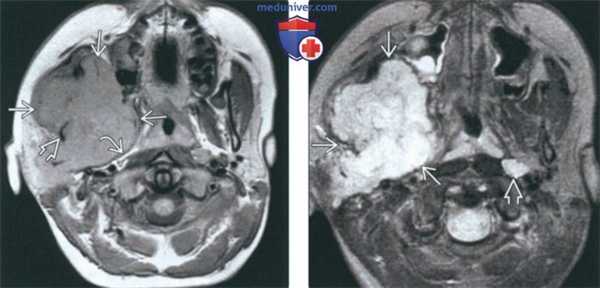

(Слева) На аксиальной КТ в костном окне у пациента с известным нейрофиброматозом 2 типа определяется расширение правого овального отверстия. Обратите внимание на неизмененное овальное отверстие слева. Такое расширение отверстий с сохранением их краевых кортикальных пластинок характерно для доброкачественных опухолей оболочки нерва.

(Справа) На корональной МРТ (Т1 ВИ С+ FS) у этого же пациента визуализируется шваннома ЧМН V3 вытянутой формы, накапливающая контраст. Опухоль начинается в параселлярной области, выходит через расширенное овальное отверстие в жевательное пространство на уровне носоглотки.

(Слева) КТ в костном окне, аксиальная проекция. У пациента установлен диагноз нейрофиброматоза 2 типа. Правое овальное отверстие расширено, в то время как размеры левого овального отверстия находятся в пределах нормы. Подобное расширение отверстий черепа без разрушения кортикального слоя характерно для доброкачественных опухолей нервной оболочки.

(Справа) МРТ Т1ВИ FS с КУ в коронарной проекции, тот же пациент. Шваннома нижнечелюстного нерва, накапливающая контраст, распространяется от параселлярной области через расширенное овальное отверстие к жевательному пространству носоглотки.